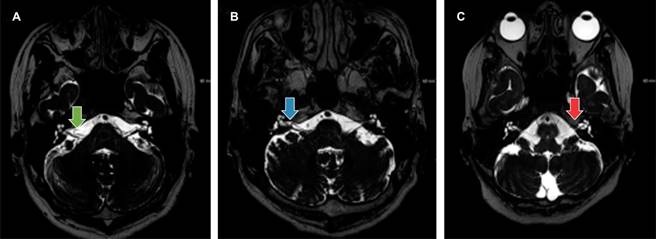

Es de utilidad la clasificación anatómica de Chavda (Figura 1) quien propone tres tipos de asas vasculares de la arteria cerebelosa anteroinferior:9

Figura 1: Clasificación de Chavda. A) Tipo I: asa de la arteria cerebelosa anteroinferior (flecha verde) a nivel del ángulo pontocerebeloso y fuera del conducto auditivo interno. B) Tipo II: asa de la arteria cerebelosa anteroinferior (flecha azul) ocupando menos de 50% del conducto auditivo interno. C) Tipo III: asa de la arteria cerebelosa anteroinferior (flecha roja) ocupa más de 50% de longitud total del conducto auditivo interno.

Asas vasculares tipo I: contacta con el nervio coclear en el ángulo pontocerebeloso, pero no entra al conducto auditivo interno.

Asas vasculares tipo II: entra al conducto auditivo interno y se extiende menos de 50% de su longitud.

Asas vasculares tipo III: se extiende más de 50% de la longitud del conducto auditivo interno.